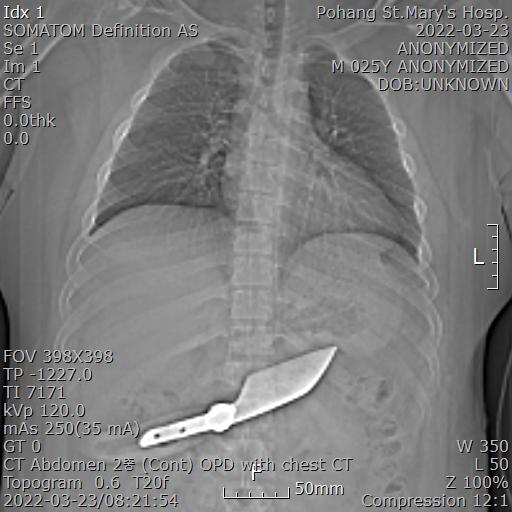

그래서 위 사진처럼 칼이 움직이지 않게 잘 고정한 후에 복부 CT를 시행했습니다.

칼이 잘 확인되는데 손잡이를 포함한 길이가 약 30cm 정도입니다.

복강내에 흰색으로 보이는 부분이 칼이고 금속인 경우 CT를 찍으면 왜곡되어서 좀더 크게 보입니다.